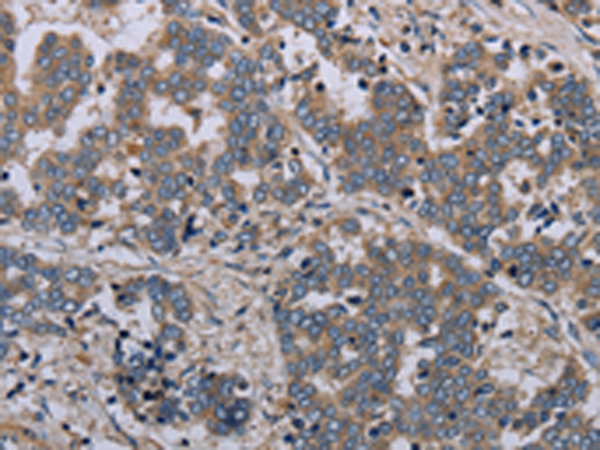

分类: 科研抗体货号: P05098别名: BAFFR; CD268; CVID4; BAFF-R; BROMIX; prolixin应用: WB,IHC反应种属: Human, Mouse